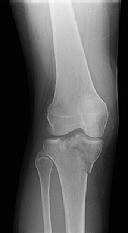

Figures 1 and 2 are the radiographs of a 35-year-old man who is brought into the emergency department after a motor vehicle collision. He is complaining of isolated knee pain. Examination reveals swelling, blood filled blisters, popliteal ecchymosis, joint line pain, and limited knee joint motion. His pulses and sensation are normal.

**CLINICAL SITUATION**

Figures 3 through 8 are the axial and sagittal CT scan sections of the injury. Intra-operative patient positioning for definitive fixation should be

The surgical approach for definitive reduction and stabilization of this pattern is